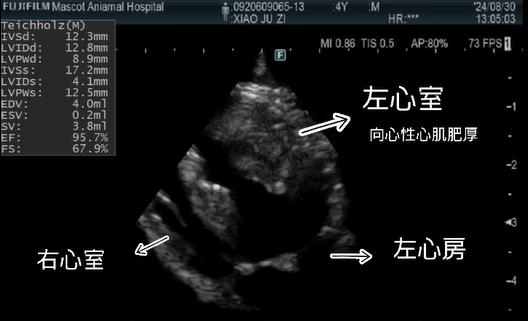

| 心臟超音波 | 心臟檢查的黃金標準。清晰觀察心臟結構、瓣膜開合、血流速度與收縮/舒張功能。 | 結構與功能 |

萌寵引進最新日本富士原廠人醫頂級超音波。其影像精確度比擬 CT 掃描,能提供高解析度的心臟結構畫面,大幅減少因影像不清晰而拉長檢查時間的問題。